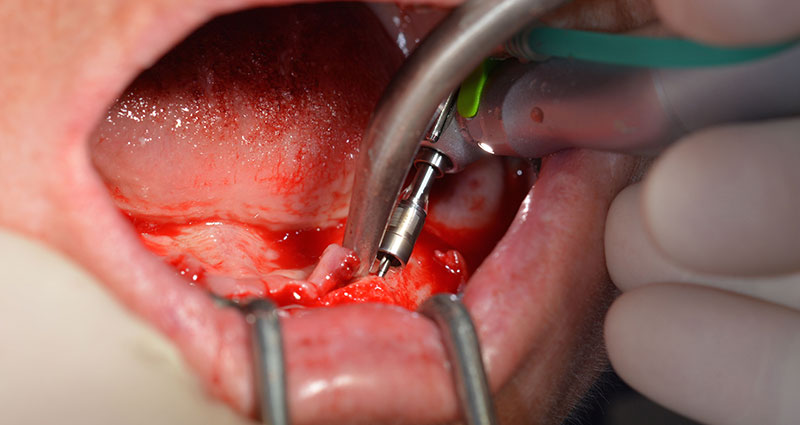

Следващият програмиран режим е за поставяне на имплантите. В нашата практика, ние обикновено използваме торг от 32 Ncm за поставяне на импланти (Фиг. 12 и 13).

Високата първична стабилност е абсолютно изискване за имедиатно въстановяване. С цел да се постигне това, отворът не е допълнително обработен. Използван е мотор Implantmed на W&H, който е оборудван със специален подходящ режим за това, който може да бъде избран директно и е необходим за много индикации. Последните навивания при поставяне на имплантите надвишават 32 Ncm и се изпълняват ръчно. В такива случаи, ние препоръчваме употребата на самонарязващата функция на имплантите и завъртане на имплантите напред-назад няколко пъти. Това позволява имплантът постепенно да достигне финална позиция без да се оказва прекомерен натиск върху костта (Фиг. 14).